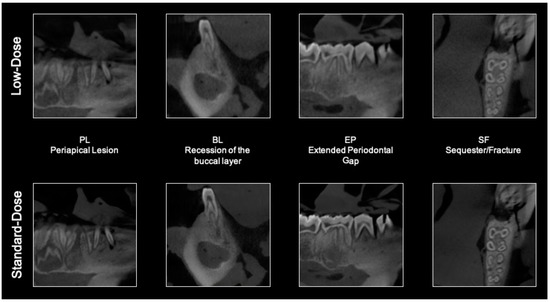

Detectability of Osseous Lesions with a Pre-Programmed Low-Dose Protocol for Cone-Beam Computed Tomography